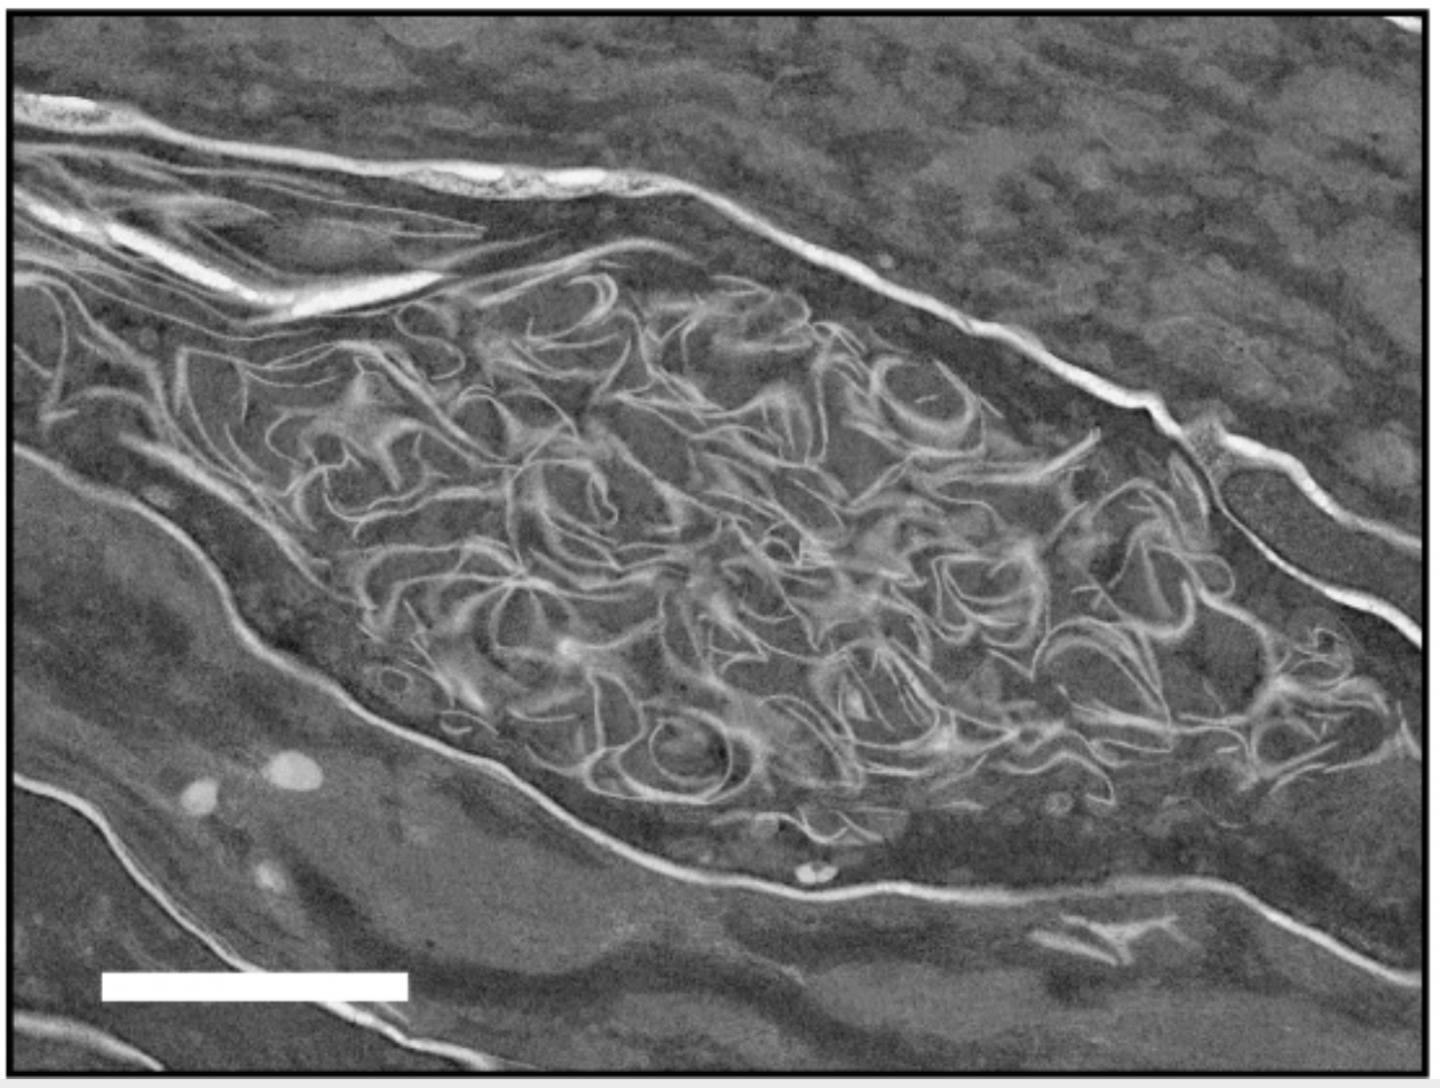

image: Abnormal membrane structure observed in the outermost skin layer of a mouse lacking FATP4. Scale: 1μn.

Investigations revealed microscopic changes in the skin similar to those that occur in people born with ichthyosis prematurity syndrome. These included abnormalities in the outermost layer of the epidermis.